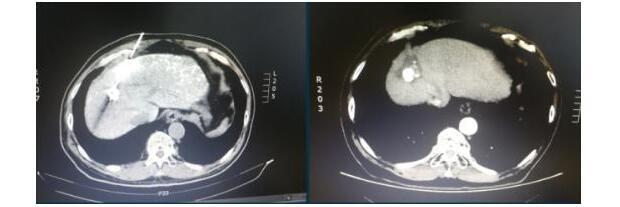

碘化油示踪小病灶准确穿刺消融

TACE联合射频消融